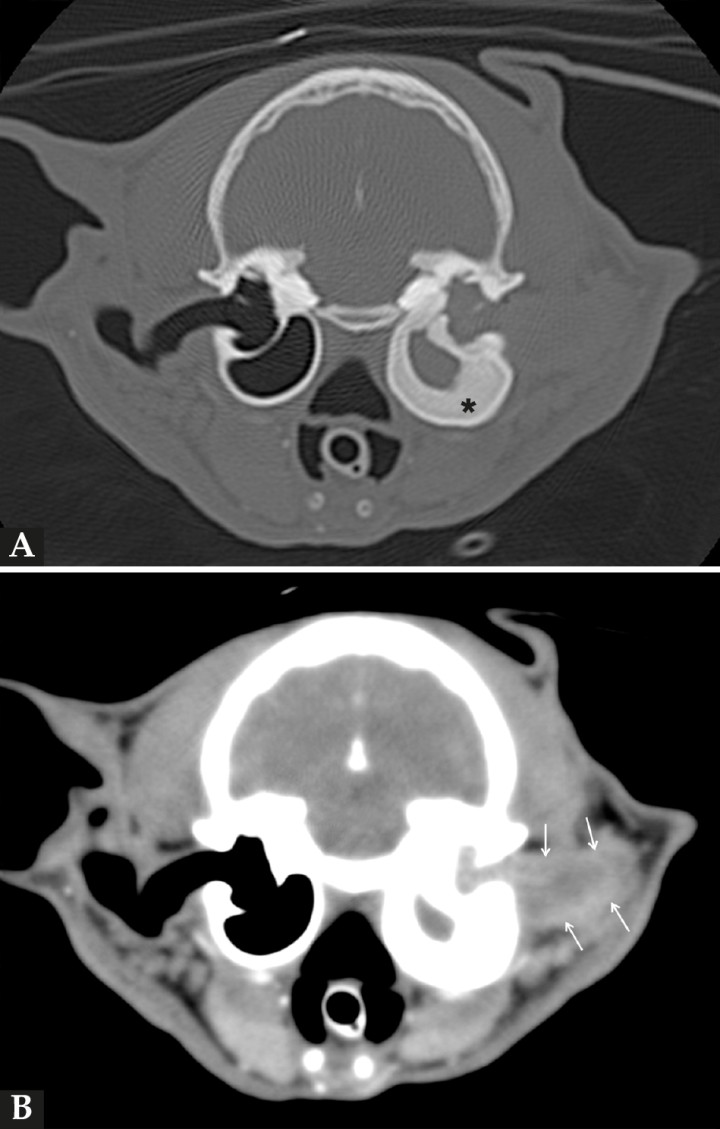

En este caso, el estudio de TC (General Electric HiSpeed dual, General Electric Healthcare, Madrid) se realizó bajo anestesia general y con el paciente en decúbito esternal. Se realizaron series pre y postcontraste (Iobitridol 300 mg I/ml; a dosis de 600 mg I/kg intravenoso, administrado de manera manual) tras su administración y pasados tres minutos (Fig. 3), con cortes de 3 mm de grosor e intervalo de 1,5 mm con algoritmo estándar (tejido blando) y hueso. El estudio de TC se evaluó en ventana de tejido blando y hueso. En la serie precontraste se visualizó la pared de la BT izquierda gravemente engrosada (5 mm) en comparación con la contralateral (1 mm), y su interior ocupado, casi en su totalidad, por un material de atenuación tejido blando (70 UH) que se extendía a lo largo de la parte horizontal del CAE, teniendo una menor atenuación (38 UH), pero con bordes más atenuados (60 UH). En la imagen inmediata a la administración del contraste se observó un moderado realce periférico o en anillo de la masa (75 UH), mientras que su interior apenas mostraba captación de contraste (44 UH). Pasados tres minutos, el realce se incrementó ligeramente en la periferia de la masa (90 UH) manteniendo una atenuación prácticamente similar en su interior (50 UH).

Imágenes de tomografía computarizada (TC) en plano transversal en ventana de huesos (A) y en ventana de tejidos blandos tras la administración de contraste (B) de la cabeza del paciente, en las que se visualiza severo engrosamiento y esclerosis de las paredes de la bulla timpánica izquierda (asterisco), cuyo interior se encuentra ocupado por material de atenuación tejido blando que se continúa hacia el conducto auditivo externo en el que se aprecia realce postcontraste de manera periférica (en anillo) (flechas).

Estos hallazgos eran compatibles con un PIA con ocupación de la BT y CAE izquierdo, asociado a una severa esclerosis de la pared de dicha bulla.

Por otra parte, la TC aporta una mayor información anatómica y permite diferenciar el contenido de la BT por su atenuación (UH). El patrón de TC característico del PIA es el de una masa bien definida y pedunculada con marcado realce en anillo tras la administración del contraste. Con respecto a la resonancia magnética, puede ser una herramienta ventajosa, sobre todo en aquellos casos en los que haya sospecha o sintomatología compatible con enfermedad neurológica.[ Shanaman M, Seiler G, Holt DE. Prevalence of clinical and subclinical middle ear disease in cats undergoing computed tomographic scans of the head. Vet Radiol Ultrasound 2012; 53(1): 76-79. [PubMed] , Lamb CR, Sibbing K, Priestnall SI. Pathologic basis for rim enhancement observed in computed tomographic images of feline nasopharyngeal polyps. Vet Radiol Ultrasound 2016, 57(2): 130-136. [PubMed] ] En el presente caso, las pruebas de imagen permitieron apreciar una lesión compatible con un PIA, poniendo de manifiesto una grave esclerosis de la pared de la BT izquierda.